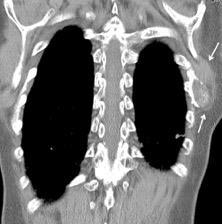

Nódulo en língula.

Cirugía de Ca .de mama hace 23 añosedema de brazo y ganglio en axila. ¡Metástasis!.